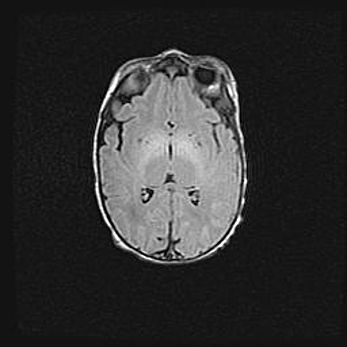

Сообщающаяся гидроцефалия. Кистозная энцефаломаляция головного мозга.

Возраст: 3 месяца 4 дня

Вес: 3100 г

Пол: женский

Окружность головы: 34 см

Срок гестации: 31 неделя

Кистозная энцефаломаляция головного мозга - одна из форм поражения головного мозга в детском возрасте. Характеризуется возникновением множественных и распространённых кист в коре, белом веществе и подкорковых образованиях головного мозга у плодов, новорождённых и детей раннего возраста. Развитие кистозной энцефаломаляции связано с внутриутробной асфиксией и гипотонией, родовой травмой, тромбозом синусов, пороками развития сосудов, инфекциями, сепсисом и другими причинами. Наиболее значимые инфекционные агенты: вирусы простого герпеса, цитомегалии, краснухи, токсоплазмы, энтеробактерии, золотистый стафилококк и другие.